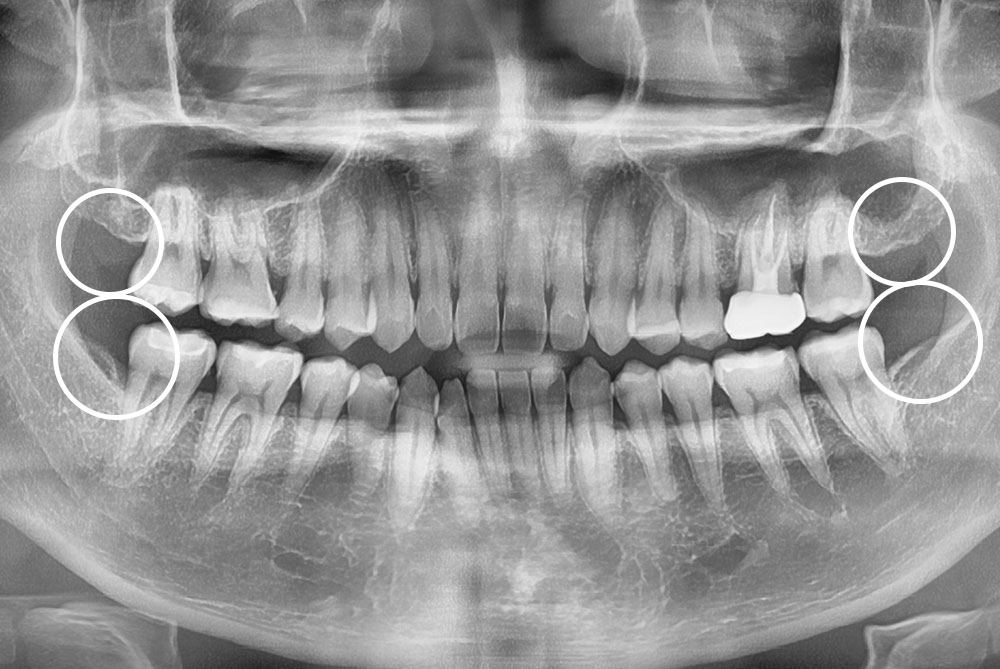

[사랑니] 매복 사랑니 발치

치료전 : 2016-09-23